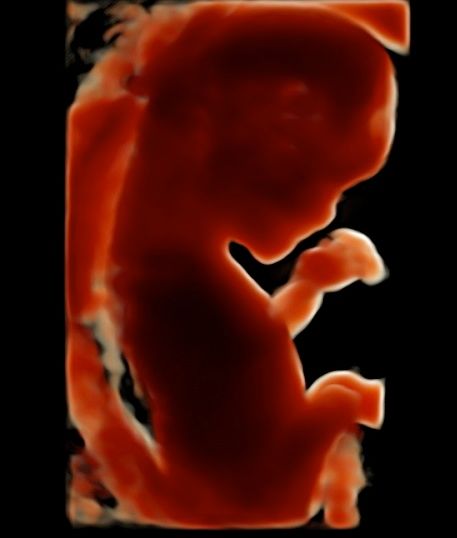

Subito dopo la laurea, il dottor Tommaso Incandela, ha conseguito l'idoneità ospedaliera nella branca di Ostetricia e Ginecologia con il giudizio finale di ottimo. Dall'Aprile 1977 fino al Gennaio 1982, su delibera del consiglio di facoltà, ha svolto la funzione di medico interno della seconda cattedra di Ostetricia e Ginecologia con mansioni didattiche, di assistenza e di cura. Dal Luglio 1981 al mese di Ottobre 1992 ha ricoperto la funzione di assistente di ruolo presso la seconda divisione di Ostetricia e Ginecologia dell'Ospedale Civico e Benfratelli di Palermo. Dal 1 Novembre 1992 fino alla fine di Giugno 1998 è stato dirigente medico del Consultorio familiare di Santa Flavia. Dal Luglio 1998 a tutt'oggi si dedica a tempo pieno all'attività libero professionale occupandosi di ecografia ostetrica e ginecologica con particolare riguardo per la diagnosi prenatale di patologie cromosomiche e malfomative (studio di aneuploidie cromosomiche su DNA fetale prelevato dal sangue materno, amniocentesi precoce, ecocardiografia fetale, ecografia morfologica e cardiotocografia) tutte queste indagini sono inserite nel monitoraggio della gravidanza. Il dottor Tommaso Incandela si occupa altresì di diagnosi precoce e terapia di patologie del tratto genitale inferiore e nel corso degli anni ha acquisito una notevolissima esperienza nell'ambito della terapia conservativa dei fibromi uterini mediante terapia farmacologica e/o inserimento di spirali medicate al progestinico. Da un punto di vista chirurgico il dottor Incandela si occupa di patologie del corpo uterino ivi compresa l'asportazione di fibromi con conservazione dell'utero stesso anche in pazienti meno giovani e con assenza di desiderio di prole. Il dottor Incandela si occupa anche di chirurgia del pavimento pelvico con particolare riguardo per la terapia dell'incontinenza urinaria, dei prolassi uterini e vescicali e delle lacerazioni antiche da parti pregressi.

• Ecocardiografia fetale

• Ecografia morfologica